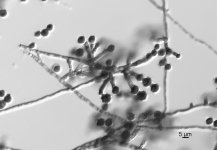

| Species Name: | Scopulariopsis brevicaulis |

| Taxonomy: | FUNGI Ascomycota, Sordariomycetes, Microascales, Microascaceae |

| Substrate: | skin biopsy of cutaneous lesion, male 26 yr with non-Hodgkin's lymphoma who underwent unrelated bone marrow transplant; histopathology + for numerous fungal hyphae in deep dermis | Location: | USA Nebraska, Omaha, University of Nebraska Medical Center (GEO: 41.255,-95.976) |

| Characters: | HUMAN/ ANIMAL PATHOGEN invasive cutaneous infection in patient with non-Hodgkin's lymphoma - fide P. Iwen // HUMAN/ ANIMAL PATHOGEN invasive cutaneous infection in patient with non-Hodgkin's lymphoma - Iwen PC, Schutte SD, Florescu DE, Noel-Hurst RK, Sigler L, Med Mycol 2012 Epub Apr 23 (Click for publications citing UAMH 10915) |